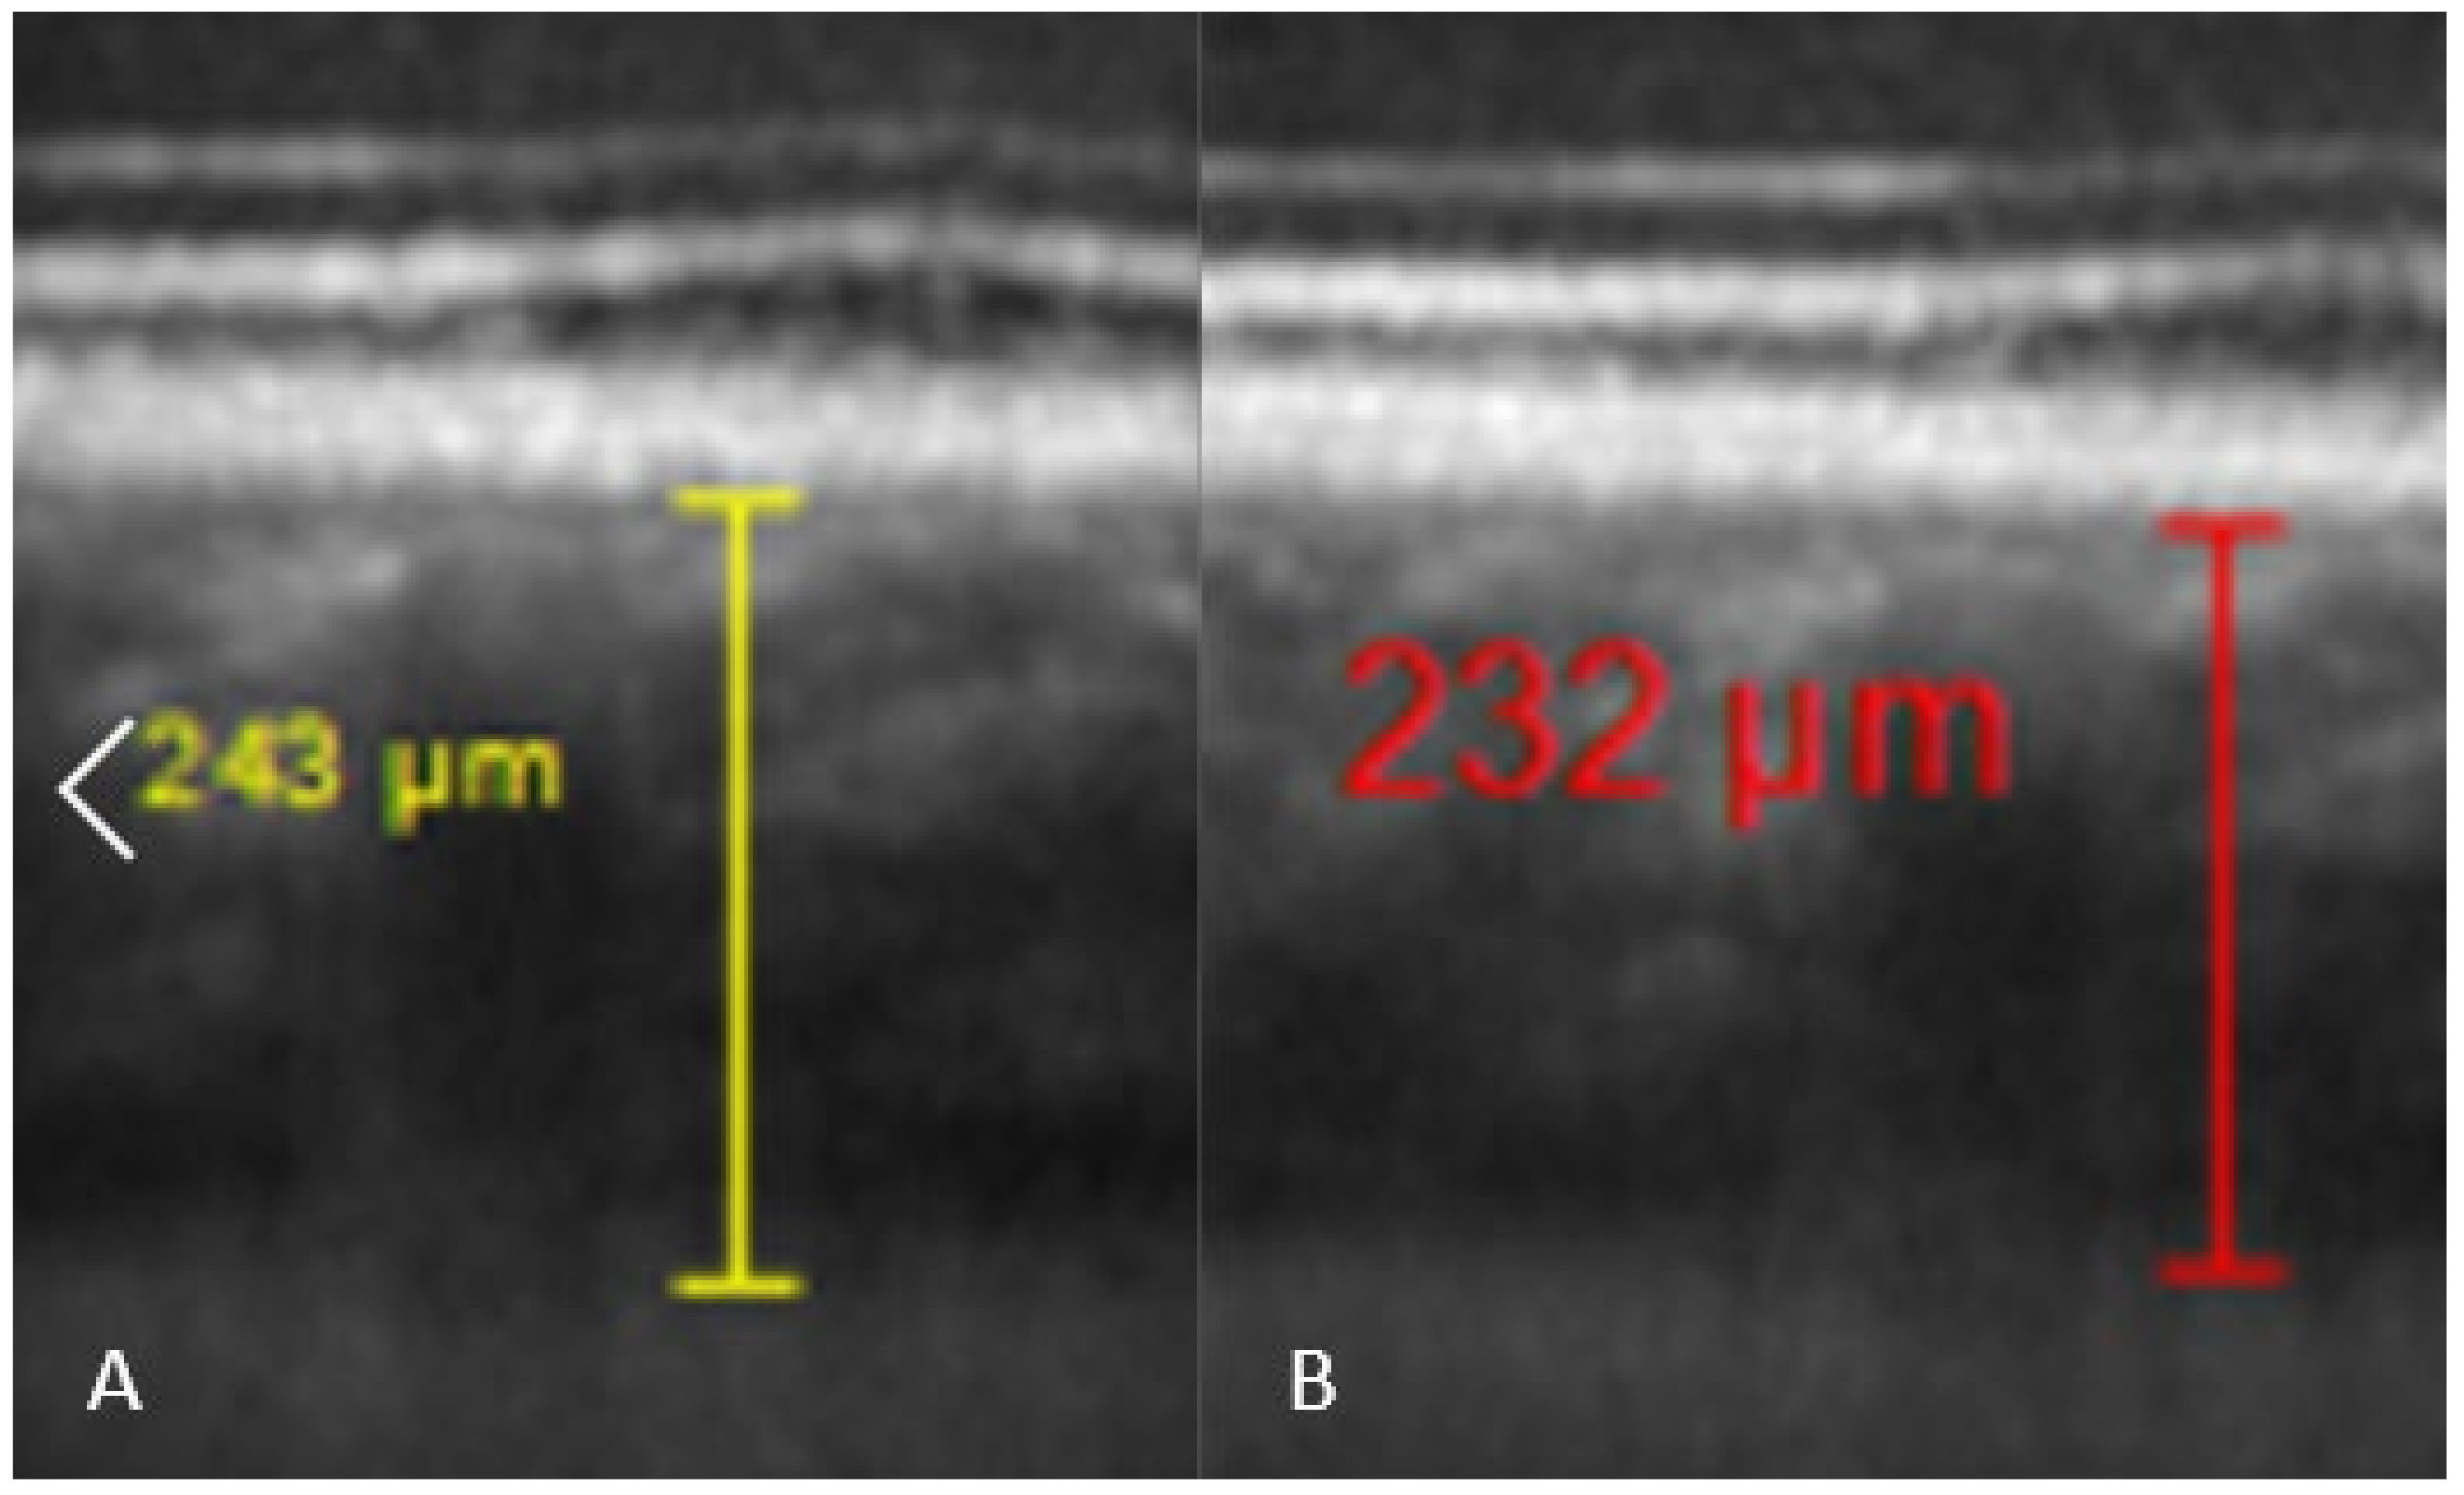

2.2.1. Ophthalmic Measurements

5.1. Subfoveal Choroidal Thickness

| SFCT (%) | 100 | 96.6 (±13.89) | 0.016 | 98.4 (±5.7) | 0.21 (ns) |

| SFCT (µm) | 327.1 (±102.0) | 318.1 (±109.7) | 0.0326 | 322.2 (±102.1) | 0.2434 |